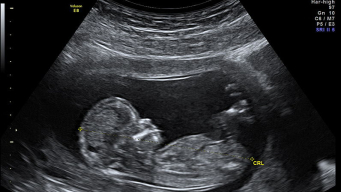

Ultrasound during pregnancy, also known as sonography, is an exam that is initially considered to have no contraindications, but it should not be overused since some studies suggest caution due to the emission of energy. During the ultrasound exam, the device uses sound waves to capture images of the fetus, uterus, and placenta. In addition to images, it can also capture internal sounds, including the fetal heartbeat.

Although ultrasound is one of the main ways for parents to find out the baby's sex, ultrasound during pregnancy goes far beyond that. It is possible to monitor fetal development and verify measurements, weight, and also the amount of amniotic fluid. You can also see the baby's features in advance through a 4D ultrasound.

In the first trimester, pregnancy ultrasound is performed to check the fetal heartbeat, visualize the gestational sac, and determine gestational age. In some cases, when done very early, before 7 weeks, the ultrasound does not show any details and the heartbeat may not be heard.

As pregnancy enters the second trimester, the most detailed ultrasound is required. The morphological ultrasound is done around 20 weeks of gestation. It is usually during this scan that the baby's sex can be seen. Throughout the procedure, the baby's heart is checked, as well as brain development, the digestive system, and the baby's entire body is measured to assess growth.

During this ultrasound exam, the position of the placenta is also monitored, as it might be covering the opening of the cervix. If so, this must be followed in future ultrasounds to see if the placenta moves before the birth.